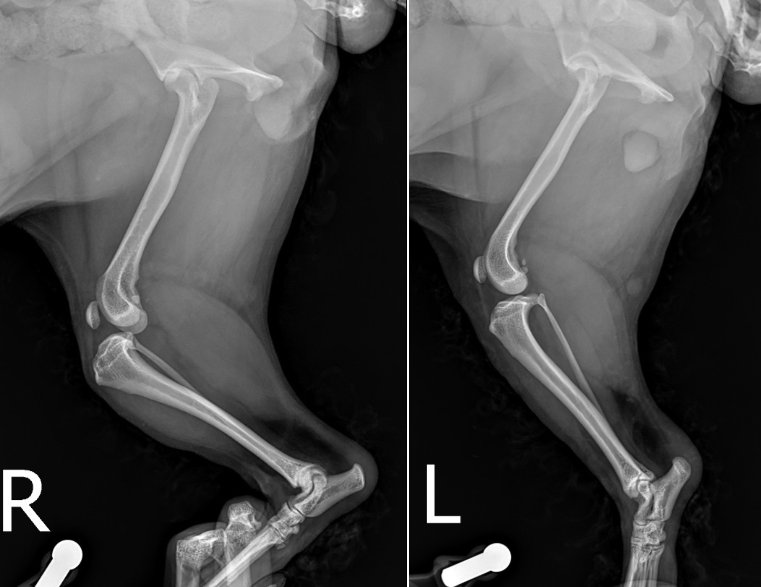

엑스레이 상 십자인대가 끊어지면서 무릎이 앞으로 밀리는 소견이 확인되었습니다.

또한 십자인대가 끊어지게 되면 급성 관절염 및 부종 소견이 동반될 수 있는데 그 또한 확인되어 종합적으로 봤을 때, 환자는 우측 십자인대 완전 단열로 인해 이미 관절염도 진행되고 있고 통증이 있는 것으로 고려되었습니다.

TPLO 수술을 계획하기 위해서는 엑스레이 촬영 했을 때 좌측에 보이는 calibration ball 을 같이 포함하여 촬영을 해야합니다. ▼

* 관절내 부종이 확인됩니다.

* 무릎을 굽힌 상태로 엑스레이 촬영 시 십자인대 단열로 인해 무릎이 앞으로 전방변위되는 것이 확인됩니다.

그리하여 명란이는 우측 십자인대 단열에 대한 TPLO 수술을 계획하게 되었습니다. TPLO 는 무릎의 각도롤 교정해서 십자인대가 밀리면서 유발되는 통증을 느끼지 못하도록 하는 수술법입니다.